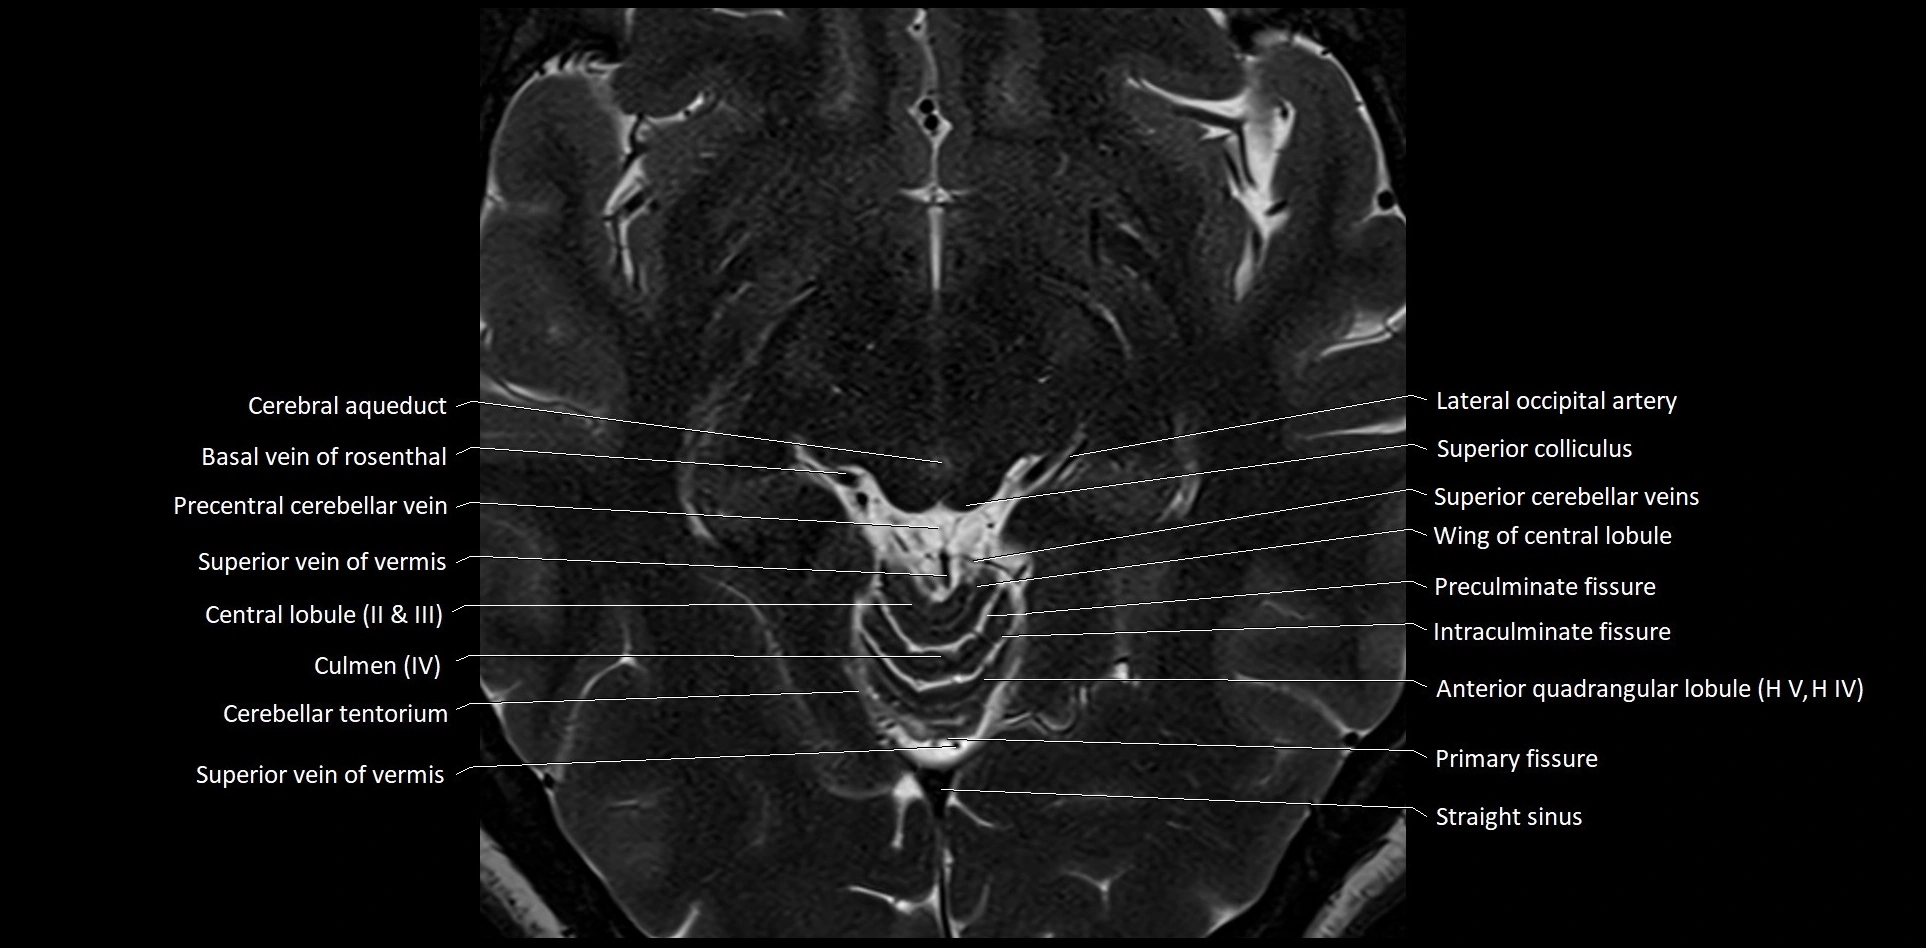

MRI images